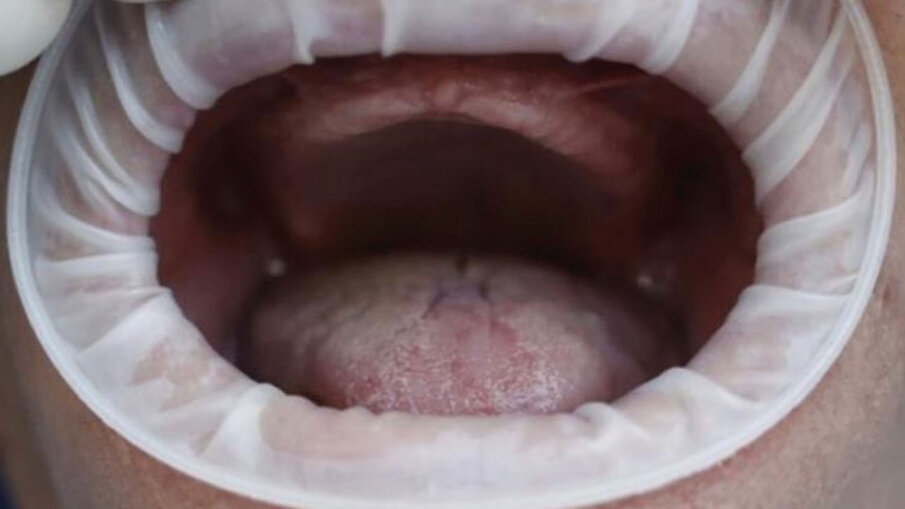

Fig. 8 - Mucosa gengivale prima della scopertura delle viti tappo e successivo inserimento dei monconi.

Lo spessore della struttura del PD presenta 44 microfori passanti che permettono allo stesso di non fare effetto barriera tra l’osso basale e il periostio sovrastante. I dispositivi si distinguono in “a carico immediato” con i monconi monolitici senza connessioni da protesizzare subito; ed “a carico differito” cioè senza monconi ma con alloggiamenti filettati per permette di avvitare in un secondo momento quattro monconi per la protesizzazione (Fig. 1). Il procedimento chirurgico prevede una minima incisione da canino a canino, scheletrizzazione con distacco della parte terminale del nervo nasopalatino, come tutti i sottoperiostei, la modellazione dell’osso residuo con piezosurgery o fresoni per accogliere la forma del dispositivo ad appoggio completo e fissazione con impianti ridotti come detto sopra. La sutura sarà a completa copertura del PD a seconda se a carico immediato o differito prevede una seconda apertura solo sulle connessioni dei monconi che hanno delle viti tappo inserite (Figg. 2-15).